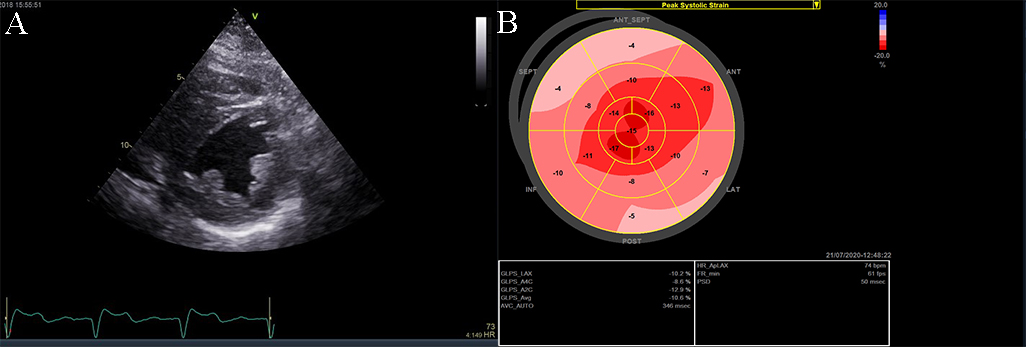

The most specific feature of the myocardium in HCM is the reduced contractile stress (the force per unit area) because of the cardiomyocyte disarray and interstitial fibrosis [33, 37]. A maintained ejection fraction is explained by the increased end-diastolic wall thickness that produces an augmented thickening, but the histopathology of this disease is characterized by myocardial hypertrophy, fiber disarray, increased loose connective tissue, and fibrosis, which are all thought to interfere with force generation and relaxation of the cardiac muscle. Both speckle tracking and tissue Doppler highlight this feature, with a significantly lower longitudinal systolic strain, systolic strain rate, and early diastolic strain rate (see Fig. 7) [27, 28, 30, 37]. GLS is independently associated with outcomes in HCM patients. A GLS with a value higher than –10 percent is associated with a higher risk of adverse events. This depressed contractility function of the LV correlates also with myocardial fibrosis and predicts ventricular arrhythmias. Through strain echocardiography an important prognostic parameter can be obtained: the mechanical dispersion, defined as the standard deviation of time from the onset of the QRS to peak negative strain. This is related to the amount of fibrosis and is also an independent predictor for arrhythmias [28].

Fig. 7.Echocardiographic aspect of HCM. (A) Apical 4 chamber view shows left ventricular hypertrophy. (B) The longitudinal strain bull’s eye plot derived from 2-D speckle tracking imaging shows a significantly reduced GLS (global longitudinal strain) of –8.1%, the most abnormal region is the basal septum, corresponding with the greatest wall thickness.